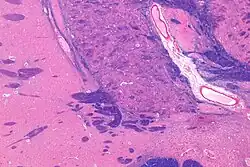

Coronal MRI slice with cross-hairs indicating location of the substantia innominata | |